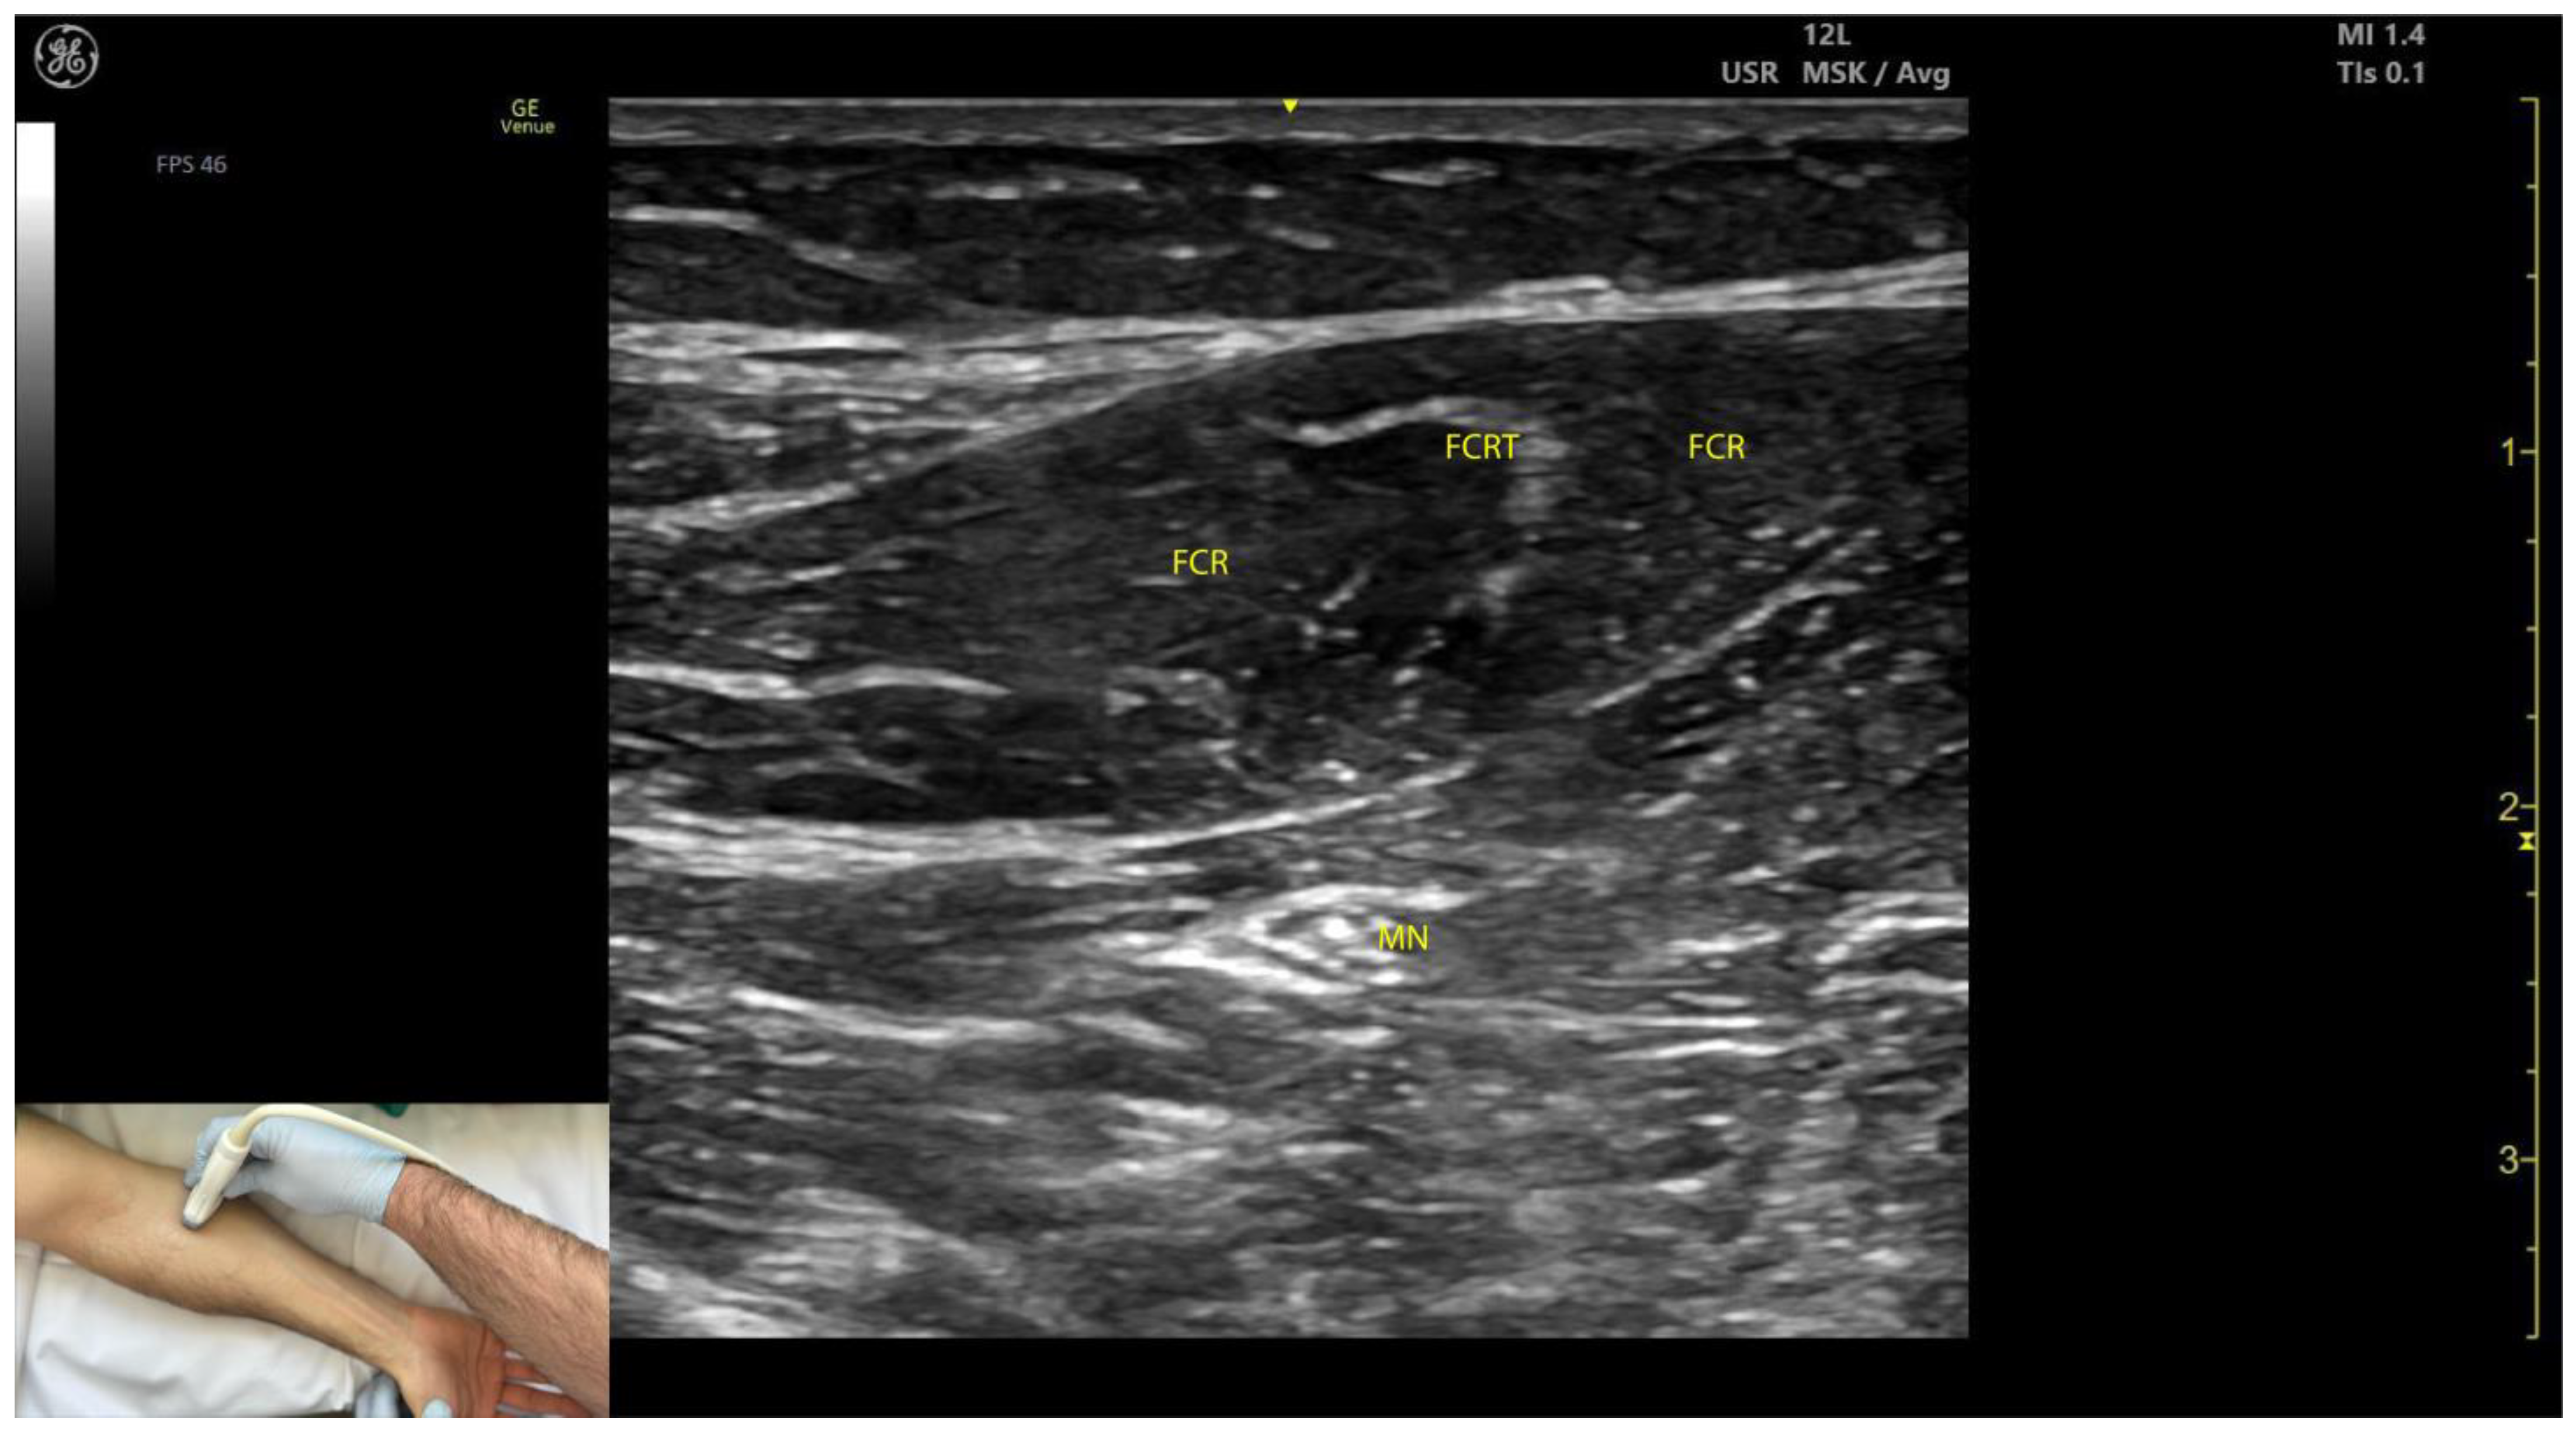

2.2.3. Key Ultrasound Landmarks (Figure 2)

- Muscle position: The FCR is the second muscle mass from radial to ulnar on the volar aspect of the forearm [20].

- Intramuscular tendon: The bipennate structure of the FCR is evident on ultrasound due to the presence of longitudinal intramuscular tendon [21].

- Median nerve: The median nerve is initially located deep to the PT, approximately 2 cm distal to the elbow crease. With distal scanning, the nerve transitions into the deeper plane of the FCR and maintains this relationship until the mid-forearm. Beyond this level, the median nerve passes deep to the flexor digitorum superficialis (FDS) [10].

- External fascia: The external fascia distinctly demarcates the FCR from adjacent muscle masses, facilitating precise BoNT-A injection.

- Dynamic evaluation: Muscle contraction is clearly visible during wrist flexion and abduction maneuvers. Scanning distally reveals an increase in the FCR muscle belly size while the PT decreases in size [11].